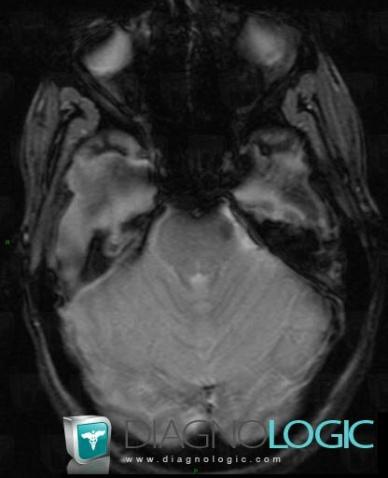

Télangiectasie capillaire, Tronc cérébral, Fosse postérieure, IRM

Voici les informations spécifiques à l'image clé ci dessus:

- Diagnostic Télangiectasie capillaire, Localisation(s) Tronc cérébral, comportant les gammes Lésion du tronc cérébralFosse postérieure, comportant les gammes Lésion infratentorielle à réhaussement modéré